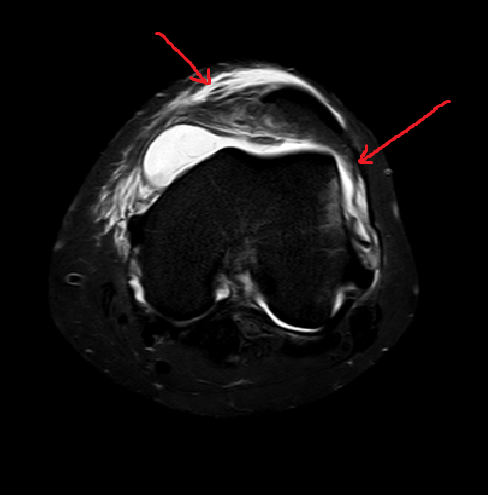

左髌股关节对位不良,股骨滑车较浅,髌骨向外侧移位,髌骨内侧缘、股骨外侧髁可

见片状压脂高信号影;内侧髌旁支持带边缘毛糙,压脂信号增高。胫股关节对位尚可

。前、后交叉韧带走行尚可,轮廓清晰,信号均匀。内侧半月板后角见条片状高信号

影,累及关节面。外侧半月板内未见异常信号影。内、外侧副韧带走行自然,未见异

常改变。关节滑膜信号混杂,髌下脂肪垫见条片状压脂高信号影。鹅足滑囊、关节腔

及髌上囊内可见液体信号影。关节前方软组织内见斑片状压脂高信号影。股内侧肌下

缘可见片状压脂高信号。

2.左膝内侧髌旁支持带损伤。

典型部位的骨挫伤,MRI表现为髌骨内下部及或股骨外髁前外侧部骨质内异常信号。

典型的韧带损伤-内侧支持带损伤。

髌骨位置异常,包括髌骨与股骨内、外髁间距的不对称改变,髌骨边缘超过股骨边缘 等。